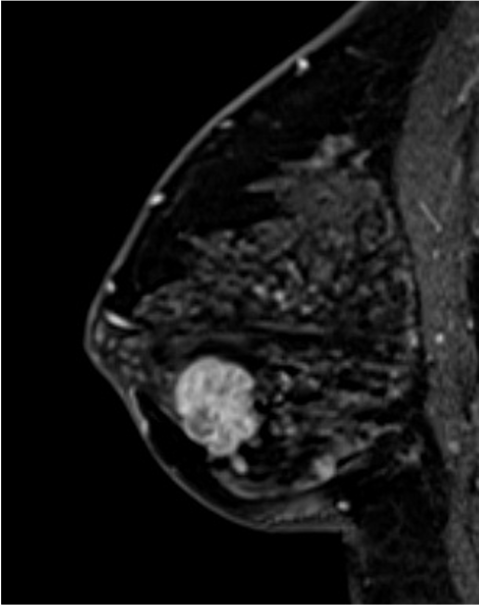

6. 造影後高分解能画像

乳癌の病変の形態は、不整形で、rim 状の造影域を認める。高分解能画像では形態的な性状を鮮明に観察できる。